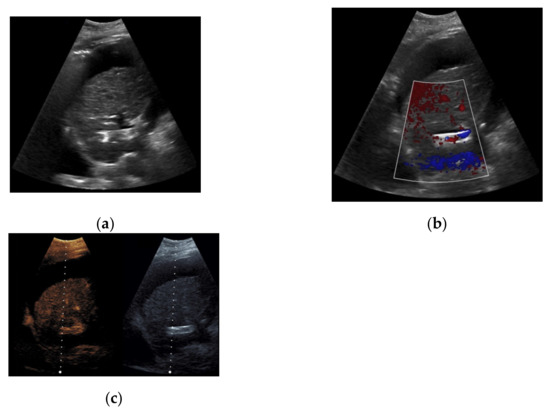

Figure 1. 65-year-old patient with regular visualization of the transjugular intrahepatic portosystemic shunt (TIPS) during B-mode (a) and adequate visualization of the TIPS in Color Doppler ultrasound (b) with inconspicuous flow and flow velocity (c).

Based on initial findings from CDUS, 67% (n = 71) of the patients showed normal perfusion within the TIPS (Figure 1). 18% (n = 19) of the cases presented stent occlusion (Figure 2) while 6% of the patients (n = 6) had partial occluding stent thrombosis (Figure 3). The TIPS perfusion in five patients was only partially assessable, while in two patients an examination was not feasible due to extensive meteorism. The patients listed under “others” showed postoperative entrapped air between the wall of the vessel and the stent (n = 2) while one patient had two TIPS, one occluded and one with a normally detectable blood flow (Table 1).